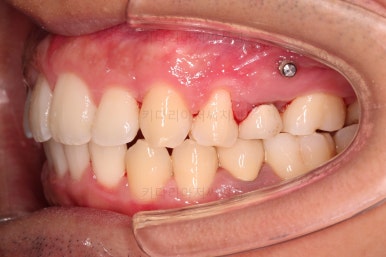

초진 시 입안의 모습입니다.

부정교합이 있고요.

옆쪽에서 보면 치아와 치아가 1:1로 부딪히는데(화살표 표시) 좋지 못한 교합입니다.

윗니와 아랫니가 앞뒤로 지그재그 서로서로 껴있어야 좋은 교합인데 전반적으로 윗니가 앞으로 밀려있는 양상의 교합이에요.

장기적으로 치아, 잇몸 건강에 좋지 못하답니다.

또한 눈에 띄는 모습은 앞니가 튀어나오고, 사이사이 틈새가 보인다는 점이에요.